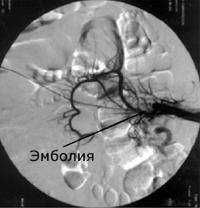

При обзорной рентгенографии брюшной полости определяется пневматизация кишечника, наличие горизонтальных уровней жидкости в брюшной полости. Специфическим методом диагностики острой окклюзии мезентериальных сосудов является селективная мезентерикография, которая уже на ранней стадии заболевания может выявить отсутствие кровотока в стволе и ветвях брыжеечной артерии. При наличии технической возможности выполняется магнитно-резонансная ангиография мезентериальных сосудов.

Непосредственной причиной острой окклюзии мезентериальных сосудов являются тромбоз и эмболия. При тромбозе просвет сосудов брыжейки перекрывается тромбом, образовавшимся вследствие изменения сосудистых стенок на фоне повышенной свертываемости крови и замедленного кровотока (патогенетическая триада Вихрова). При эмболии наблюдается обструкция брыжеечных сосудов частицей тканью опухоли, инородным телом или пузырьком воздуха, мигрировавшими от первичного источника поражения с током крови.